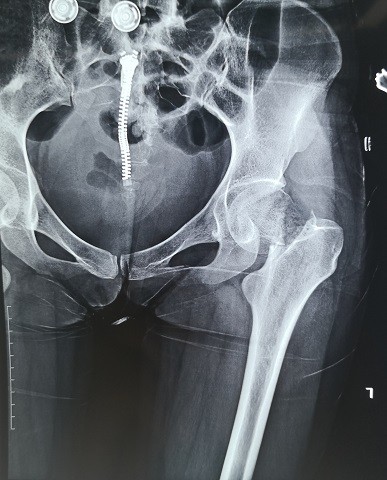

游离腓骨治疗股骨颈不愈合